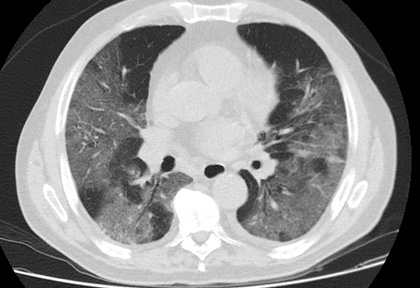

Routine clinical laboratory assays were performed in the hospital’s clinical laboratories. Clinical and laboratory information was extracted from the patients’ medical records. C reactive protein (CRP) in plasma was measured by immunoturbidimetry (Beckman Coulter, Krefeld, Germany). Interleukin-6 (IL-6) levels in plasma were measured by electrochemiluminescence (Siemens Medical Solutions Diagnostics, Siemens Healthcare, Erlangen, Germany). CT scans were read by experienced radiologists who scored results by severity using the criteria shown in Figure 1.

Figure 1. Clinical assessment of pneumonia severity based on computed tomography (CT) scores.

Scoring method: Mild (CT-1)—no more than three ground-glass opacities of <3 cm maximum diameter. Moderate (CT-2)—more than three ground-glass opacities; less than 50% involvement by visual assessment. Medium-heavy (CT-3)—ground-glass opacities and pulmonary consolidation; 50-70% involvement by visual assessment. Severe (CT-4)—diffuse ground-glass opacities with or without consolidation; more than 75% involvement by visual assessment.